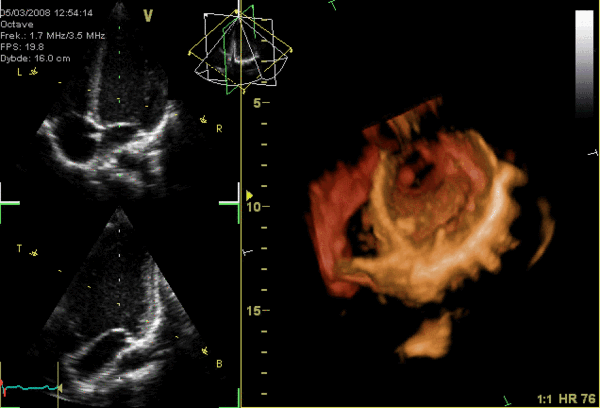

04超声下的心脏跳动图